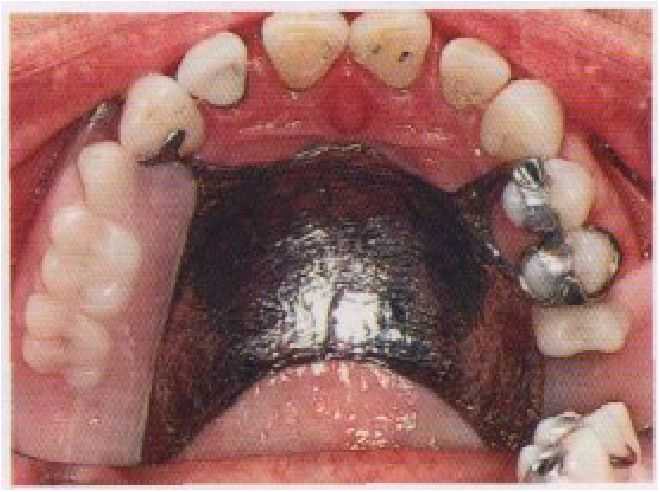

Рис 3-10 Примеры частичных съемных протезов: (а) на верхней и (б) на нижней челюсти где элементы протеза расположены таким образом, чтобы оставить свободным десневой край. (С разрешения проф. В, 0*al 1.)

Покрытие десневого края, в частности, связано с ухудшением гигиены, увеличенным образованием зубного налета, поэтому его следует по возможности избегать (рис. 3-10). Если же это невозможно, то часть съемного протеза, покрывающая десну, должна также опираться на зуб и быть изолированной от десневой бороздки. Неправильное создание указанной опоры приведет к травме тканей десны во время экскурсий съемного протеза при жевании. Изоляция перекрытого десневого края без адекватной опоры на зуб вызовет пролиферацию и гипертрофию тканей десны с заполнением ею образовавшегося свободного пространства.